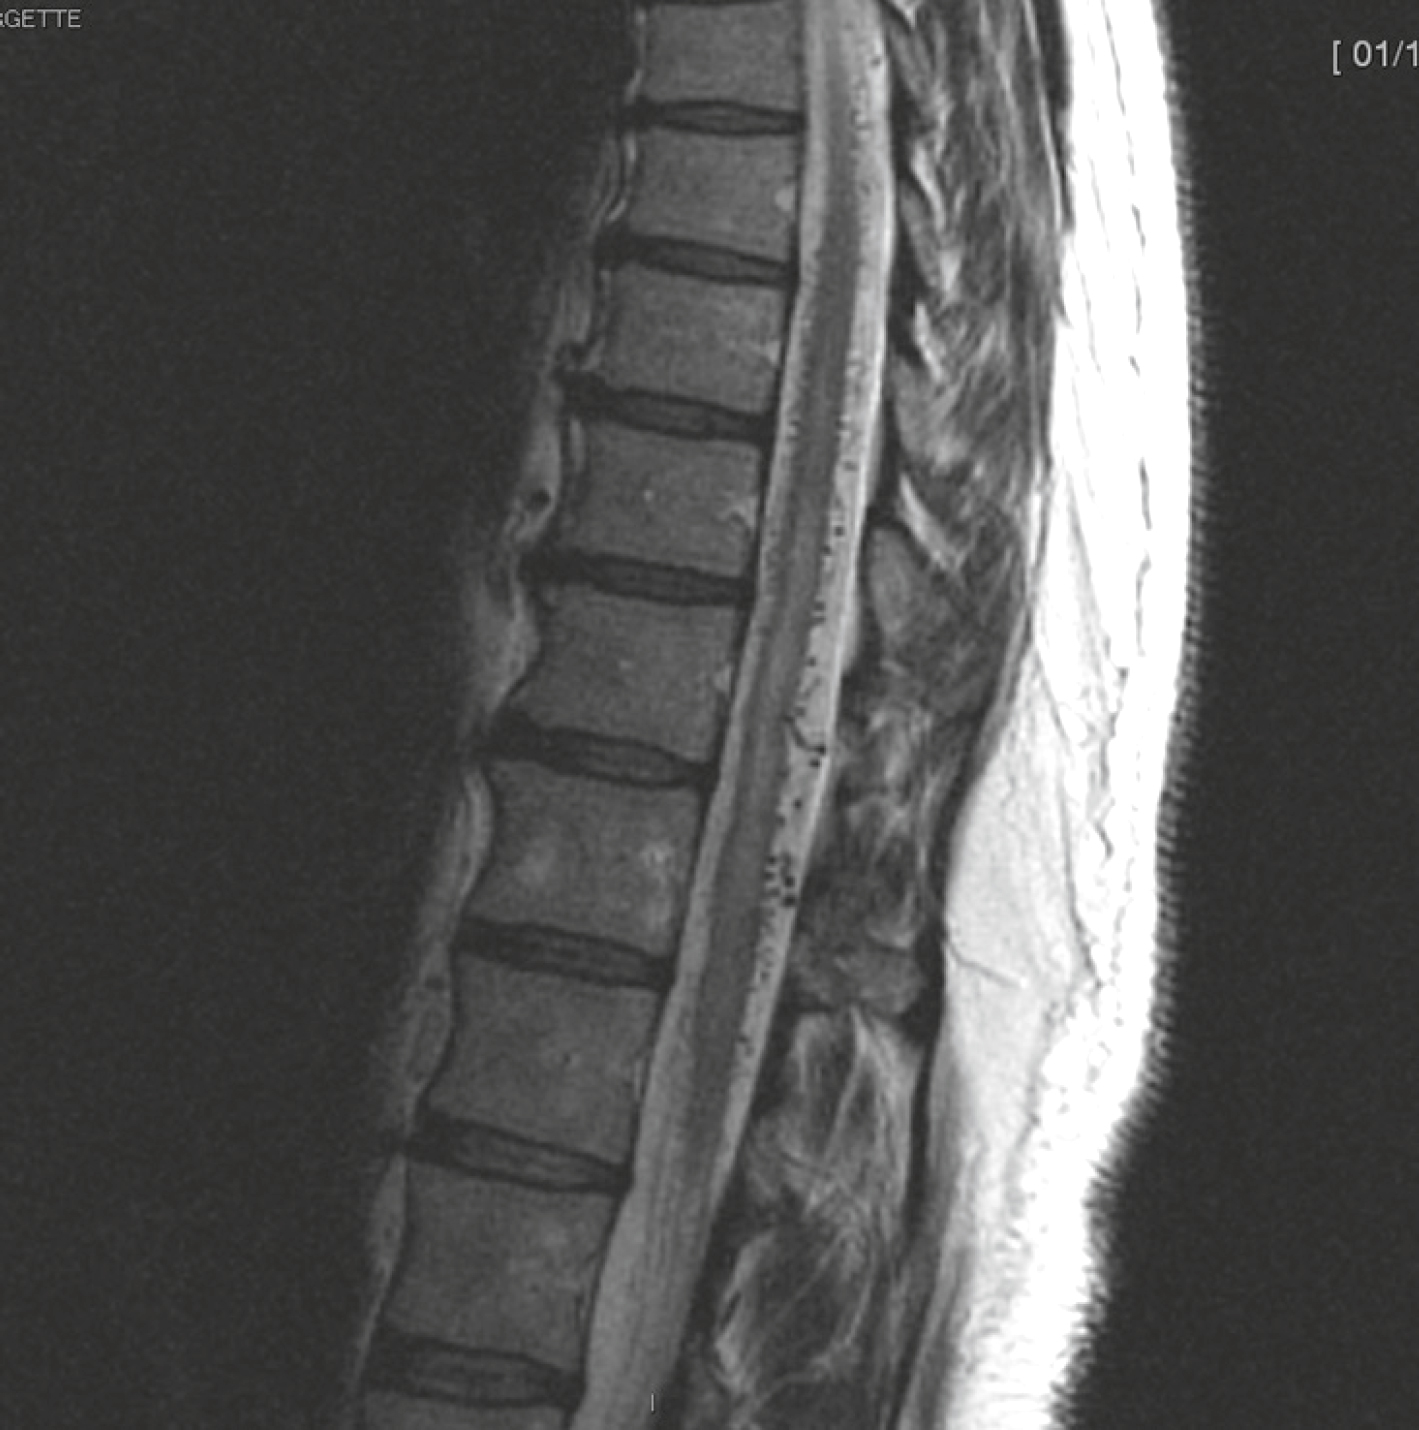

Volumineux processus expansif du cône terminal étendu de T8 à L1, en hyposignal T1 et T2, avec quelques prises de contraste nodulaires au sein de la lésion après injection. Pas de prise de contraste radiculaire; intégrité des corps vertébraux. A. Sagittal T2.

et C. Sagittal T1 sans puis après injection de gadolinium.Les coupes sagittales thoraciques en pondérations T2 (A), T1 sans injection (B) et T1 avec gadolinium (C) révèlent une lésion intramédullaire allongée, étendue sur plusieurs étages thoraciques moyens. En T2, on observe un hypersignal diffus avec une expansion de la moelle, traduisant une infiltration tumorale. En T1, la moelle apparaît élargie, avec un signal iso- à hypointense. Après injection (C), la prise de contraste est discrète, hétérogène et peu marquée, ce qui oriente vers un astrocytome, tumeur gliale souvent infiltrante, non encapsulée. L’absence de nécrose centrale ou de rehaussement net différencie cet aspect de celui d’un épendymome.